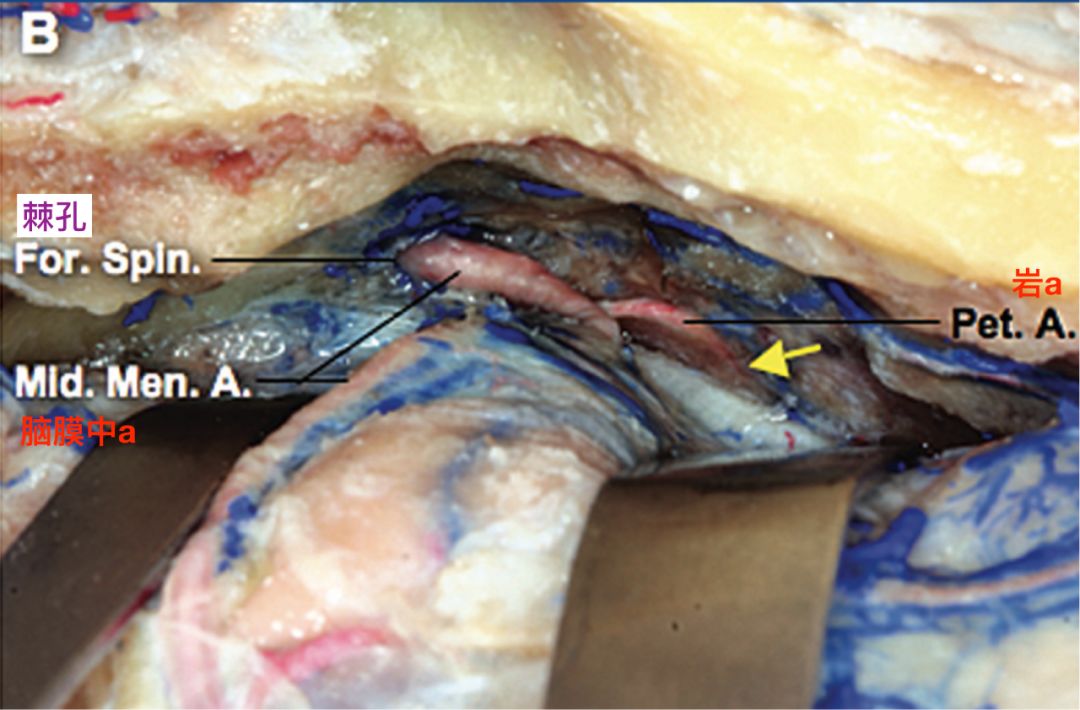

抬起中颅窝底的硬脑膜,显露岩动脉自脑膜中动脉的发出点。岩动脉在其起点远端进入中颅窝底的骨质(黄箭)(El-Khouly 2008)。

显示岩动脉发出后,穿入中颅窝底的骨质内(El-Khouly 2008)。